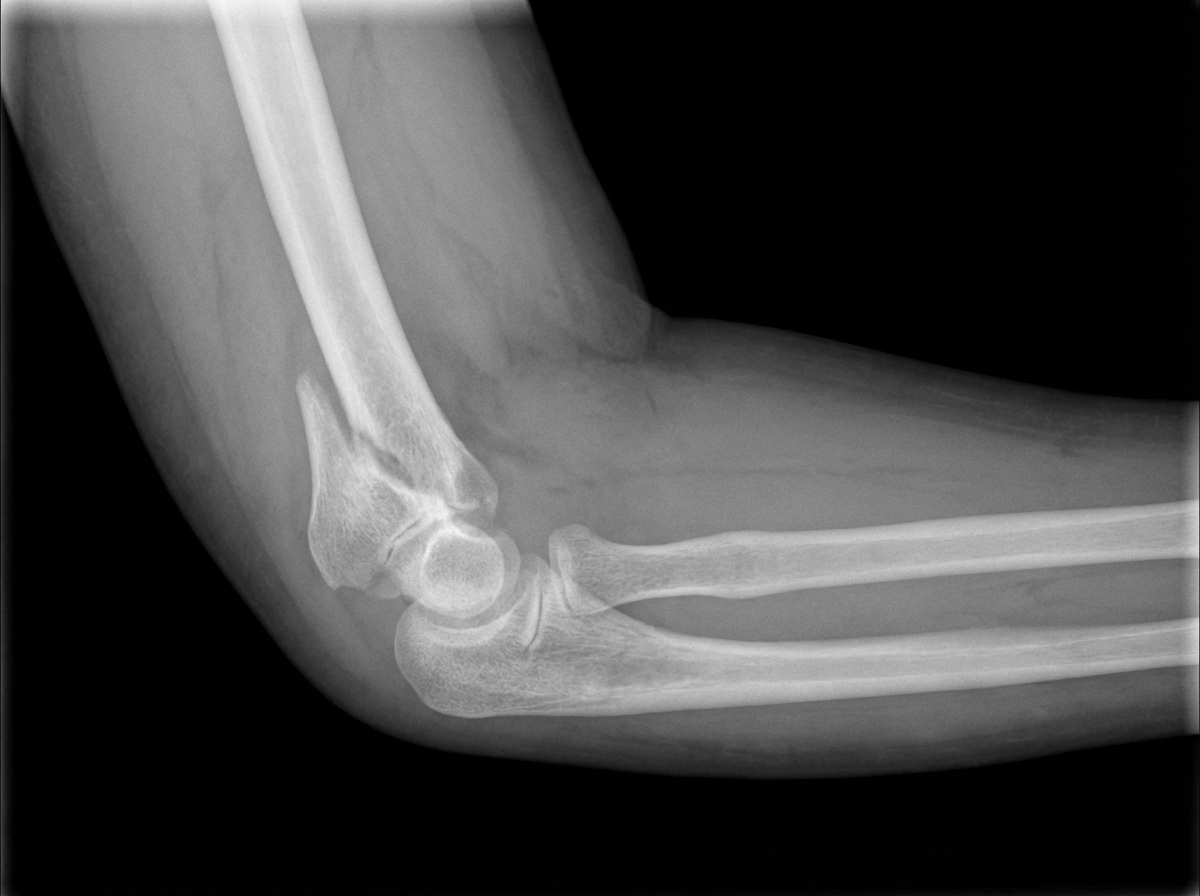

What is the X-ray diagnosis?

Explanation: ***Supracondylar humerus fracture*** - The **anterior humeral line** does not pass through the middle third of the **capitellum**, a key radiographic sign for supracondylar fractures. - This is the **most common pediatric elbow fracture**, typically occurring after a fall on an outstretched hand with hyperextension injury. *Olecranon fracture* - Would show a clear **fracture line** through the **olecranon process** of the ulna, which is not present here. - Typically causes inability to actively extend the elbow due to **triceps muscle disruption**. *Humerus shaft fracture* - The fracture line would be located in the **mid-shaft** of the humerus, not near the elbow joint. - Associated with **radial nerve palsy** causing wrist drop and loss of thumb extension. *Elbow dislocation* - Shows **displacement** of the radius and ulna relative to the humerus with loss of normal joint alignment. - The **radiocapitellar line** would not pass through the center of the capitellum in true dislocations.